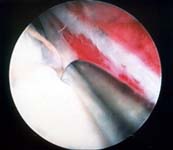

Arthroscopic surgery to remove or repair torn menisci is the definitive treatment for meniscal tears. See Figures 6 and 7.

Surgery is the definitive treatment for torn meniscus. The surgery is done arthroscopically and will include either removal or repair of the torn part of meniscus. Repair can be done only when the tear lies in or just adjacent to the vascular zone of the meniscus.

Because only the outer 20-25% of the meniscus has blood supply, repairs are successful when the tear occurs in this vascular region of the meniscus. Tears in the non-vascular region are unlikely to heal and therefore are removed.